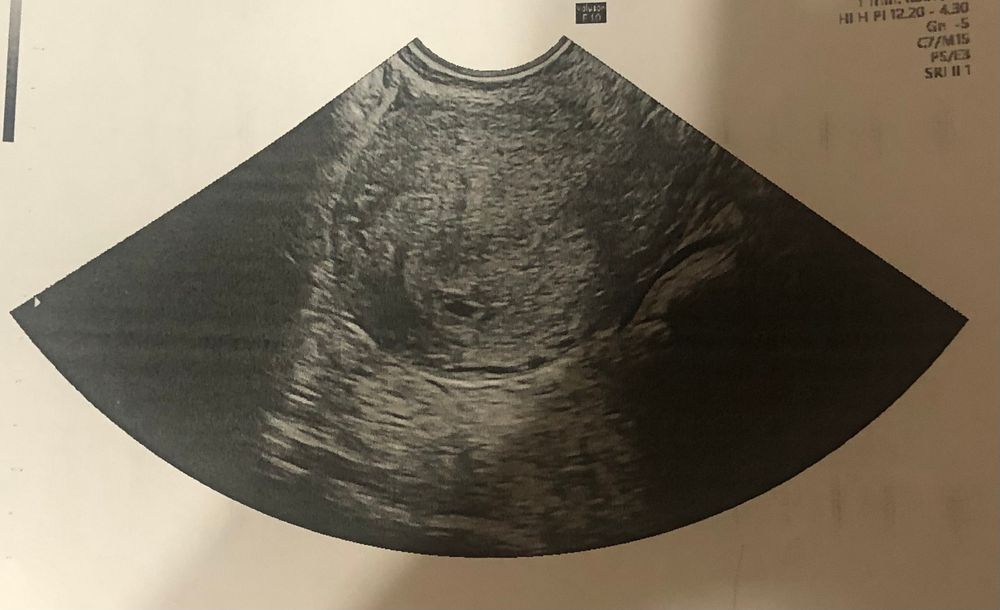

Уже подтвердила маточную беременность )